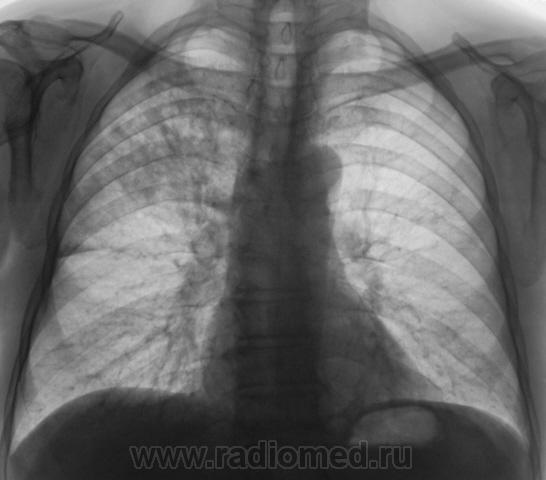

Произведена рентгенограмма в прямой стандартной проекции и томограммы в стандартных срезах.

«Пневмония», сразу показалась какой-то «фердиперсовой», с учетом лечения в стационаре ранее, довольно хорошего самочувствия пациента и наличием весьма «убогой» клиники. После проведения исследования было рекомендовано провести противовоспалительное лечение, исследование мокроты с целью проведения дифференциальной диагностики, рекомендована консультация фтизиатра.

Мы в протоколе, конечно, отметили, о возможности инфильтративного туберкулёза, д/д ряд даже не дали.

Но, мы стойко несмотря ни на что, стояли на тубере.

Пациент 4 месяца, по полной программе отлежал в областной конторе, ЦВК утвердило «инфильтративный». После выписки был направлен под надзор фтизиатра по месту жительства. Ниже иллюстрации после выписки.

Снимки сегодня.